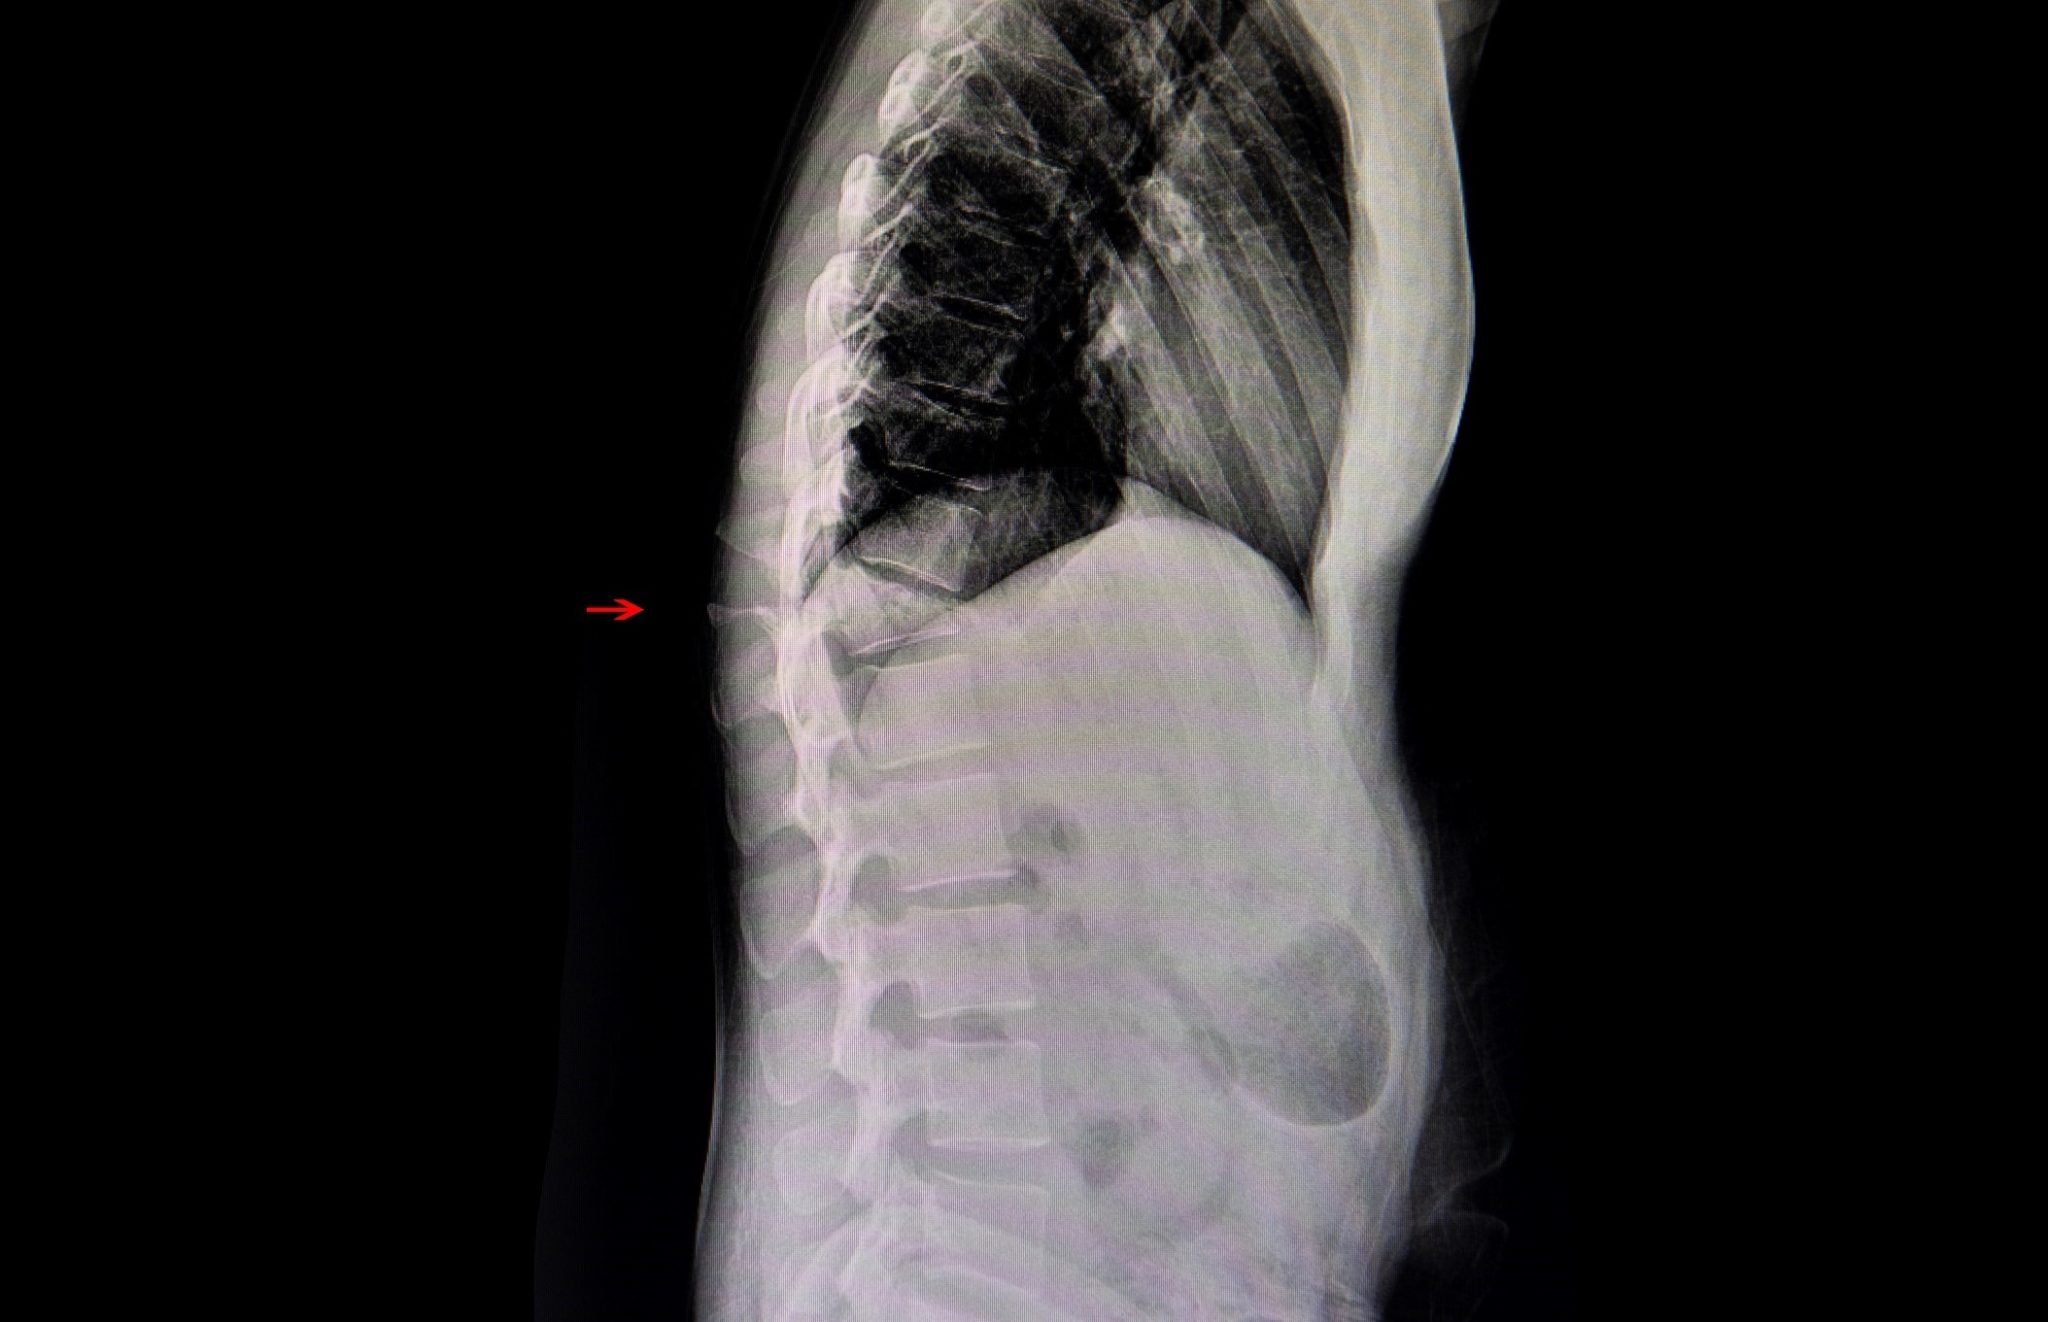

Case Study L5 Vertebral Pathological Fracture Management Compression Fracture Pain Relief Osteoporosis is the most common cause of compression fractures. most people find that medication, activity modification, and a back brace can reduce pain and allow the spine fracture to heal. More surgery to join spine bones together. Spine specialists at nyu langone recommend. pain relief was assessed by the presence or absence of pain as referred by the. Compression Fracture Pain Relief.

Compression Fracture Lumbar Compression Fracture Pain Relief most experts believe that pain relief is achieved through mechanical support and stability provided by the bone. a compression fracture is a type of break in the bones in your back that stack up to form your spine. the efficacy of osteoporotic treatment in patients with new spinal vertebral compression fracture pain, adl,. pain relief was. Compression Fracture Pain Relief.